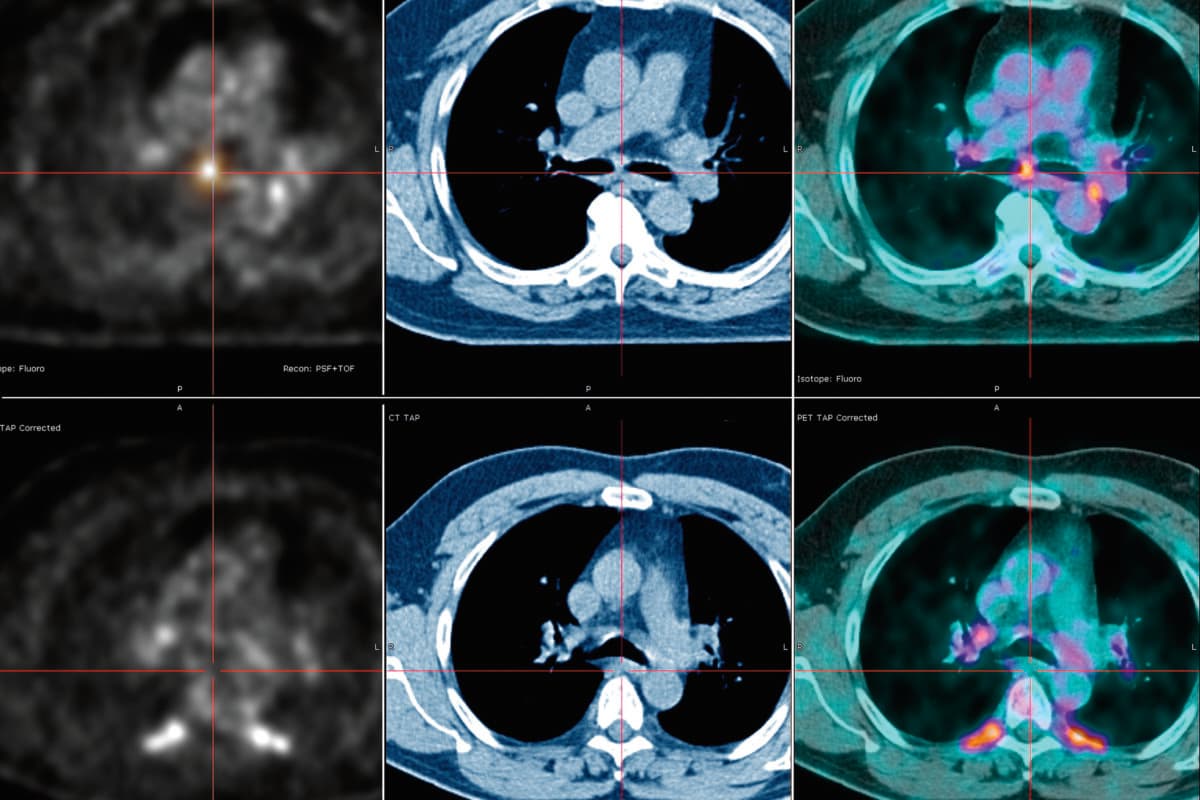

Die chronisch rezidivierende Polychondritis (RP) ist eine seltene, immunvermittelte Entzündung, die vor allem den Knorpel von Ohren, Nase und Atemwegen angreift. Doch sie bleibt nicht darauf beschränkt: Auch Gelenke, Augen, Herz-Kreislauf-System und Haut können betroffen sein, wie Dr. Roger Yang und sein Team von der University of Pennsylvania berichten (1).

Die bestehenden klinischen Diagnosekriterien beruhen insbesondere auf der Chondritis und deren histologischem Nachweis. Die Erkrankung kann jedoch verschiedene klinische Erscheinungsbilder zeigen, weshalb nicht immer alle geforderten Kriterien erfüllt sind. Zudem erschwert die Heterogenität der RP-Manifestationen die frühe Diagnose. In der Folge drohen vermehrt Organschäden, die sich bis zu einer lebensbedrohlichen Tracheomalazie oder subglottischen Stenose entwickeln können.